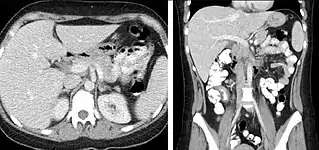

Liver masses

When evaluating hepatic masses, it can be advantageous to have both late arterial and portal venous phase images (biphasic imaging, figure 4) since some tumors enhance briskly during the arterial phase (hepatocellular carcinoma, hepatic adenoma, follicular nodular hyperplasia (FNH), and hypervascular metastasis), but may be occult or difficult to characterize on portal venous phase imaging alone (figure 6). However, it should be stressed that the addition of late arterial phase images is only indicated if one of these tumors is suspected, or if there is a need for further characterization of a hepatic mass, since the large majority of patients will not benefit from the addition of this phase. In addition, if there is a need to definitively characterize a hepatic mass, MRI is generally more sensitive and specific, with no associated radiation dose.

Transient hepatic attenuation differences in the arterial phase may mimic diseases of the liver.